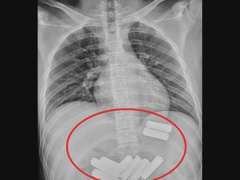

Cái kết đắng cho người đàn ông cố tình nuốt 11 viên pin vào bụng

Người đàn ông đã phải trải qua gần một tiếng đồng hồ nội soi đau đớn để lấy dị vật ra ngoài.